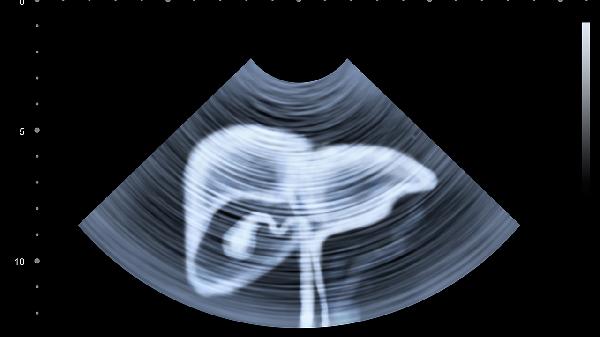

3、定期体检不能少

每年要做一次肝脏超声和甲胎蛋白检查,有乙肝病史者要缩短至半年一次。早期发现的小肝癌治疗几率可达90%以上。